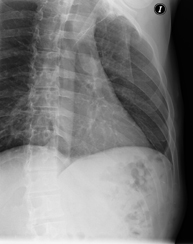

- RX Tórax

Técnica mediante la cual, utilizando rayos X, se obtienen imágenes de la caja torácica (corazón, pulmones, arcos costales, clavículas, etc.) para su estudio. - RX Esternón

- Chest X-ray

A chest X-ray uses a small dose of radiation to obtain a two-dimensional image of the thoracic cavity and its contents (lungs, heart, mediastinum, etc.). It is one of the most commonly performed medical tests.